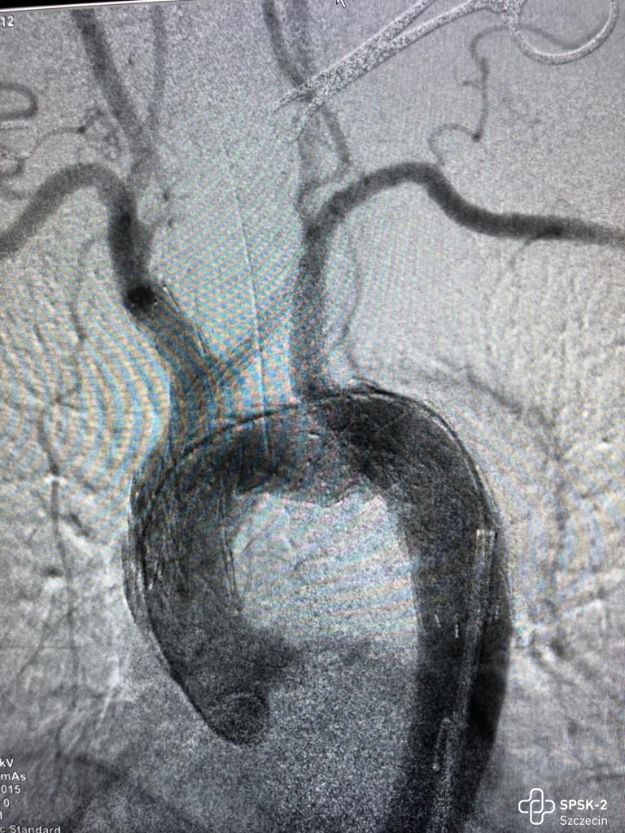

Zespół lekarzy operujących. Od lewej: dr Paweł Rynio, dr hab. Arkadiusz Kazimierczak z kliniki na Pomorzanach, oraz doktor z kliniki w Holandii. Fot. SPSK2

Chirurdzy z tzw. aortic team Szpitala Klinicznego nr 2 przy al. Powstańców Wielkopolskich w Szczecinie w ubiegłym tygodniu wykonali niezwykle trudną i nowatorską operację. Pacjent jest już wypisany do domu.

Chodzi o zabieg wszczepienia do tętniaka łuku aorty stent-graftu z wewnętrznymi rękawkami. Wyjątkowość operacji polega na wykorzystaniu aż trzech rękawków prowadzących krew do głowy i kończyn górnych.

Niezwykłością tej operacji było także to, że tętniak schowany głęboko w klatce piersiowej został zaopatrzony z dwóch nakłuć pachwin i dwóch małych nacięć na szyi pacjenta, bez potrzeby otwierania jamy brzusznej. Rekonwalescencja po takim zabiegu przebiega błyskawicznie – następnego dnia pacjent został wypisany do domu i czuje się dobrze.